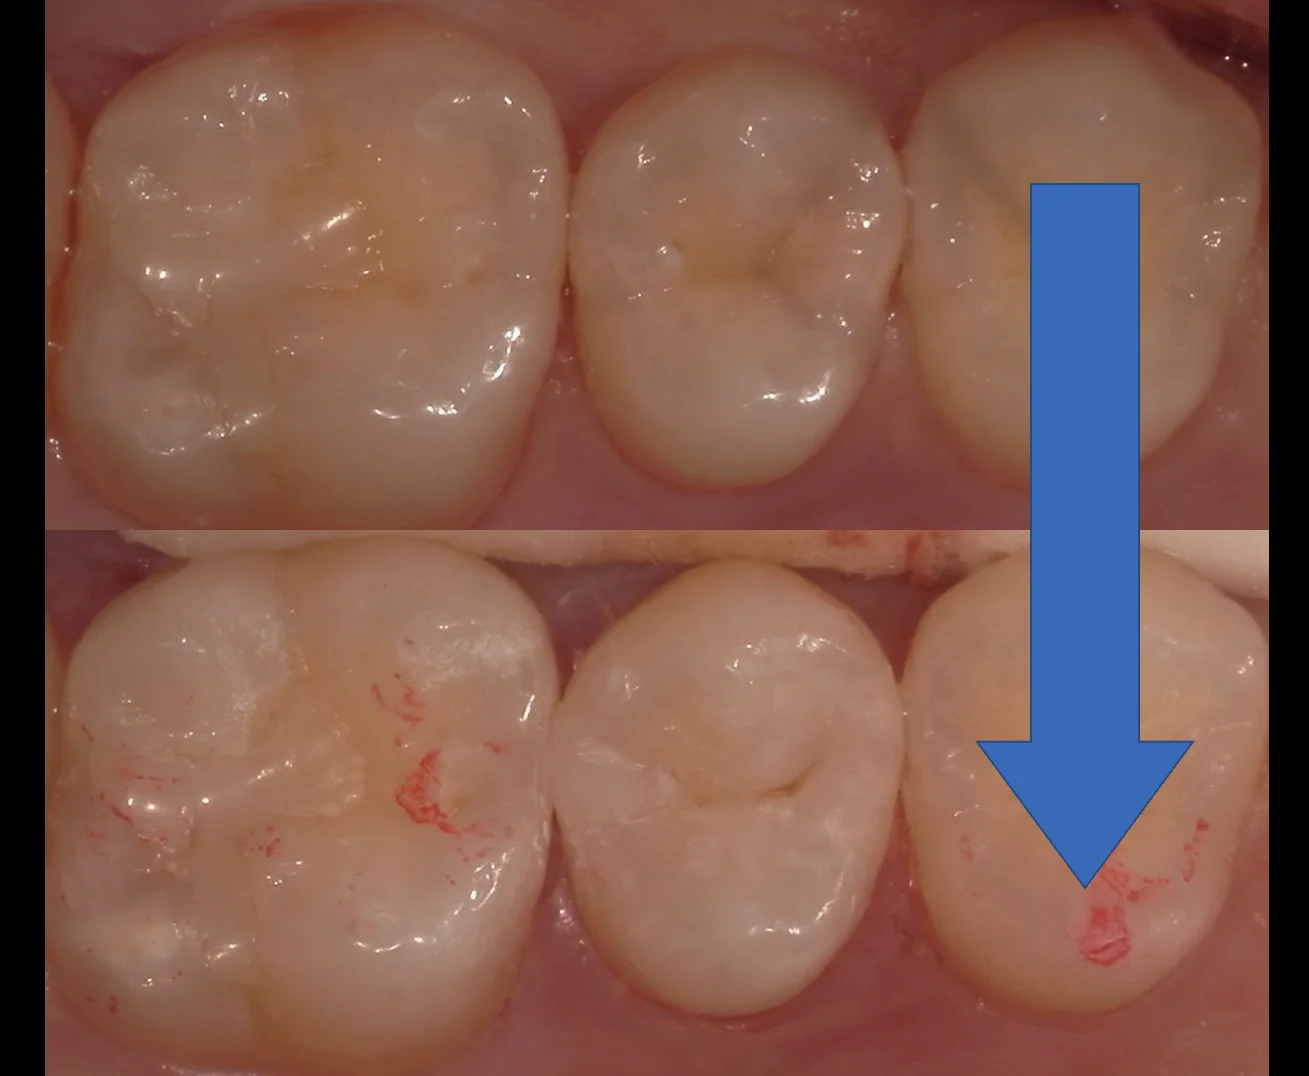

3人目はこちらの、竜ヶ崎市にて開業されている歯科医師の方です。

こちらが処置当日の写真ですね。

少し前すぎてカメラがあまりいいものではないため、画質が荒いです(⌒-⌒; )

その3年半後の写真がこちらになります。

著変なく状態は安定しているのがわかるかと思います。

この方は歯との間にも詰めているのですが、歯茎の状態も非常に良好なのがわかるかと思います。